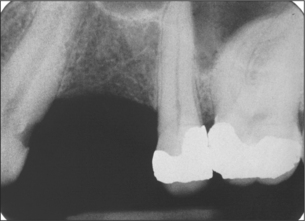

The maxillary sinus is often referred to as the maxillary antrum (or more simply the ‘antrum’). It is important to the dental surgeon because of its close relationship to the posterior maxillary teeth (generally from first premolar to third molar). The proximity varies between individuals (Fig. 15.1) but tends to increase with age as the antrum enlarges. The antrum can encroach into alveolar bone after tooth extraction, and periapical bone loss resulting from dental disease may further decrease the amount of bone separating it from the teeth. This close anatomical relationship can lead to diagnostic difficulties because both the antrum and the maxillary teeth are innervated by branches of the maxillary division of the trigeminal nerve. In addition, infection may spread from the periapical region of the posterior maxillary teeth to the antrum (and in the opposite direction) and the antrum is at risk of iatrogenic damage during certain dental procedures.

Fig. 15.1 (a) A small maxillary antrum that does not reach the apex of the second premolar. (b) A large maxillary antrum that reaches to the apex of the lateral incisor.